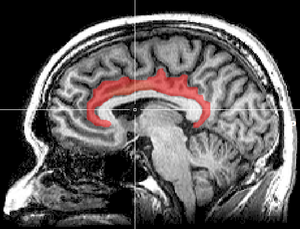

Sagittal MRI slice with highlighting indicating location of the cingulate cortex.

القشرة الحزامية cingulate cortex، تعرف أيضاً بالقشرة الحوفية، هي جزء من المخ يقع في الجانب الإنسي من القشرة المخية. القشرة الحزامية تشمل التلفيف الحزامي بأكمله، والذي يقع فوق الجسم السفني مباشرة، ويستمر حتى التلم الحزامي. القشرة الحزامية عادة ما تعتبر جزءاً من الفص الحوفي.